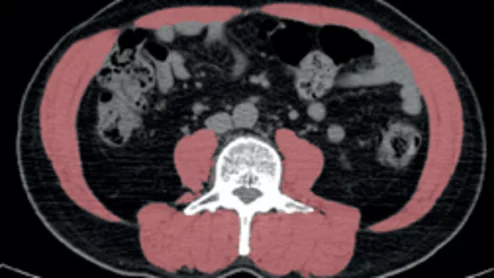

Obesity can improve lung cancer outcomes, but only if skeletal muscle quality is maintained

New research findings could help explain the “obesity paradox,” wherein being overweight is linked to both improved outcomes in certain diseases and increased mortality rates in others.